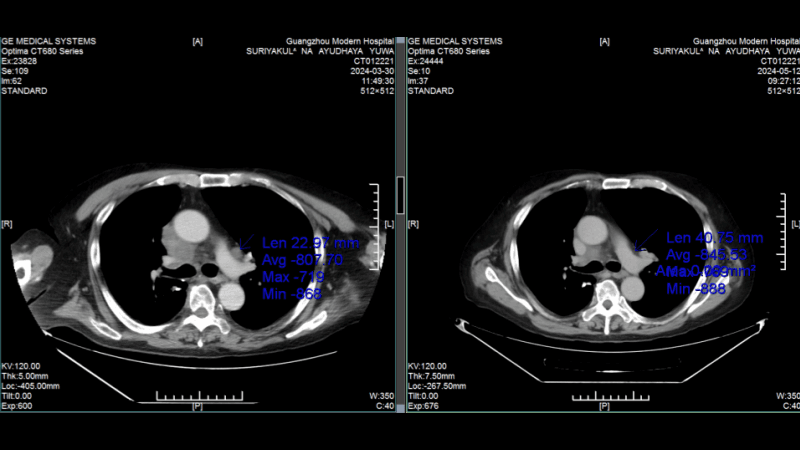

История победы: тайский генерал против рака легких с метастазами

70-летний Сурьякул На Аюдхая Ювануд нашел спасение в малоинвазивных технологиях после рецидива рака

В 2021 году у генерала Ювануда из Таиланда диагностировали рак легких. Несмотря на операцию и курсы химиотерапии, болезнь вернулась с метастазами. Возраст и гипертония сделали дальнейшее традиционное лечение невозможным. К 2023 году состояние ухудшилось: одышка, слабость, необходимость в инвалидном кресле. Семья не сдалась. По рекомендации друга, победившего рак гортани в той же клинике 10 лет назад, генерал обратился в Modern Cancer Hospital Guangzhou.

Прорыв: комплекс малоинвазивных методов

Мультидисциплинарная команда клиники разработала персонализированный план: 1. Интервенционная терапия - доставка химиопрепаратов непосредственно в опухоль через артерии. 2. Имплантация радиоактивных частиц - точечное уничтожение метастазов. 3. Иммунотерапия - активация собственных защитных сил организма. Результат через 2 курса лечения: • Опухоль уменьшилась на 60%. • Исчезли одышка и необходимость в инвалидном кресле. • Риск синдрома верхней полой вены устранен. «Интервенционная терапия бьет точно в цель, не затрагивая здоровые ткани. Это главное преимущество», - отмечает супруга генерала.

Жизнь после лечения Сегодня генерал Ювануд: • Самостоятельно передвигается и путешествует. • Вернулся к активной жизни без болей и одышки. • Проходит поддерживающую терапию с уверенностью в будущем. Его супруга добавляет: «Врачи не только продлили ему жизнь - они вернули ему её качество».